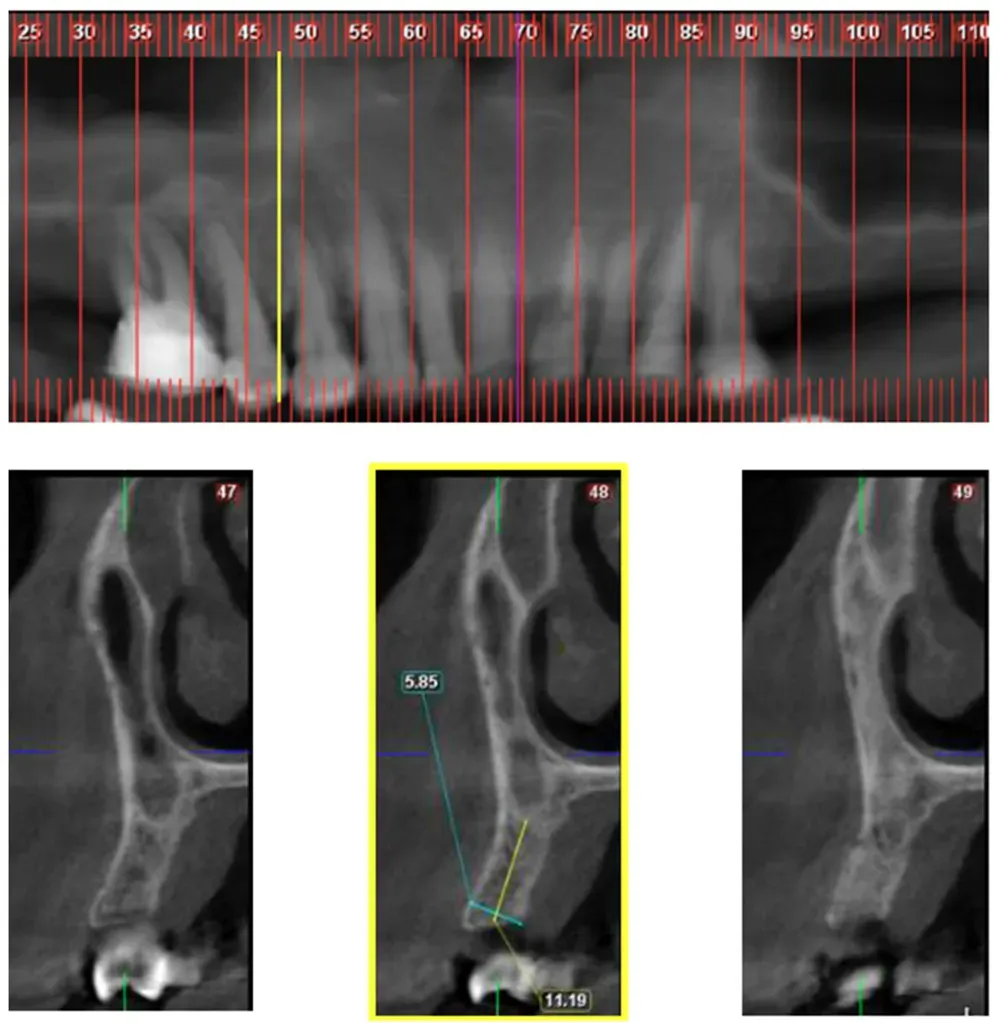

Yahya e collaboratori hanno sviluppato un sistema di classificazione che divide questa variante in classi orizzontali mesio-distali e divisioni verticali. Ma ciò che sorprende di più in questo interessante articolo è la frequenza relativamente alta della variante riscontrata dagli autori. (https://doi.org/10.3390/jcm10194293)

La Classe 2, dove il confine naso-sinusale si trova tra il margine distale del canino e quello del secondo premolare, appare nel 66% dei casi esaminati. La Classe 3, con il confine distale al margine mesiale del primo molare, si manifesta nel 16,8% dei pazienti.

Queste caratteristiche anatomiche possono essere diverse tra un lato e l’altro. È possibile riscontrare una classe su un lato e una morfologia diversa sull’altro. Vedi le immagini che seguono.